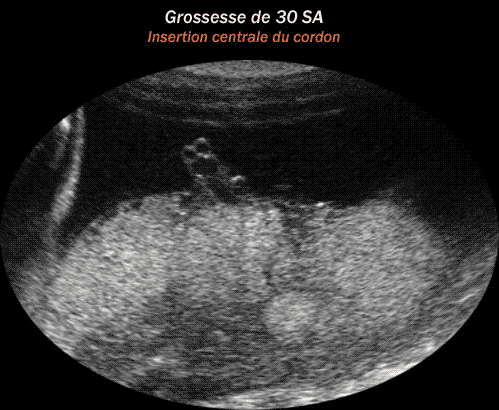

Placenta d'une grossesse à 30 semaines d'aménorrhée avec insertion centrale du cordon ombilical

sur la face placentaire ftale